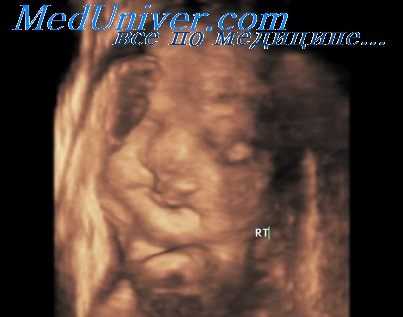

- Фетометрия плода. Ультразвуковое измерение окружностей головы, живота, грудной клетки, бипариетального и лобно-затылочного размеров, длины трубчатых костей предоставляет объективные данные о развитии плода. Полученные показатели сравнивают с нормативными для каждого периода гестации.